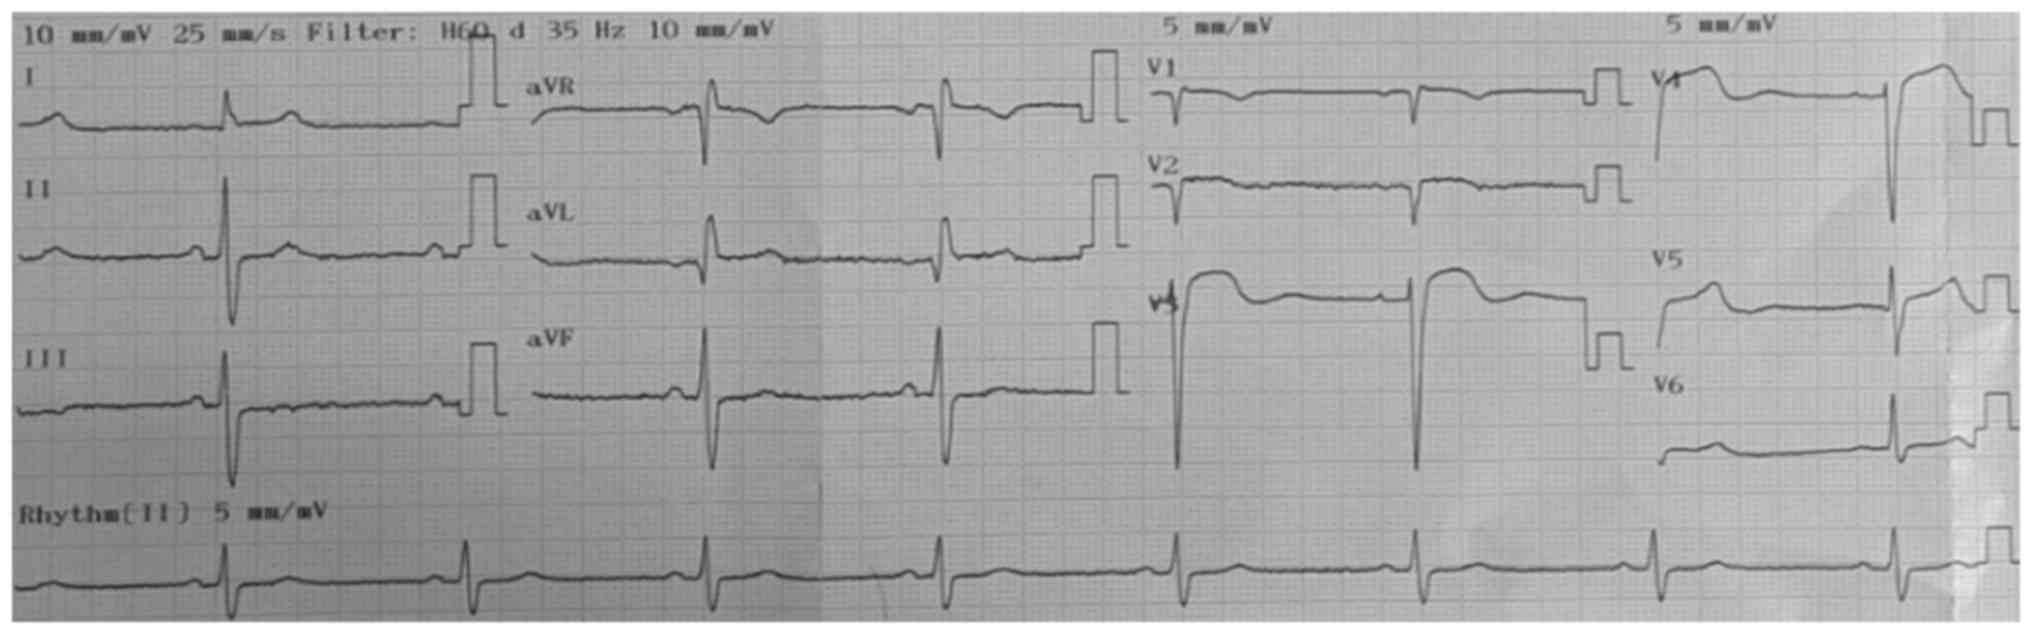

A 78-year-old male patient was transferred from a lower-complexity to a high-complexity hospital in August 2021 because imaging and hemodynamic services were unavailable in the former setting. At the lower-complexity hospital, the patient presented with weakness and decreased muscle strength in the left half of the body with 2 h of evolution, which was associated with dysarthria and deviation of the right labial commissure. The patient was admitted with elevated blood pressure (220/110 mmHg), for which 20 mg of labetalol was administered intravenously. An ECG was immediately performed, which revealed elevation of the ST segment, a situation that was managed pharmacologically as a myocardial infarction by administering 80 mg of atorvastatin and 300 mg of clopidogrel. Subsequently, the patient was transferred to a higher-complexity hospital, where it was observed that the patient neither had a history of angina or dyspnea, nor symptoms of a coronary syndrome. Fig. 1 presents ST-segment elevation in V1, V2 and V3 (acquired at the low-complexity hospital). Fig. 2 depicts ST-segment elevation in V3 and V4 (acquired at the high-complexity hospital) and Fig. 3 presents right temporal intraparenchymal hematoma with vasogenic edema and ventricular involvement (acquired at the high-complexity hospital).

Figure 2

Electrocardiogram performed at the high-complexity hospital in August 2021 during the first 30 min after the patient's admission to the hospital. Sinus rhythm, heart rate of 50 beats per min, and ST-segment elevation in V3 and V4.